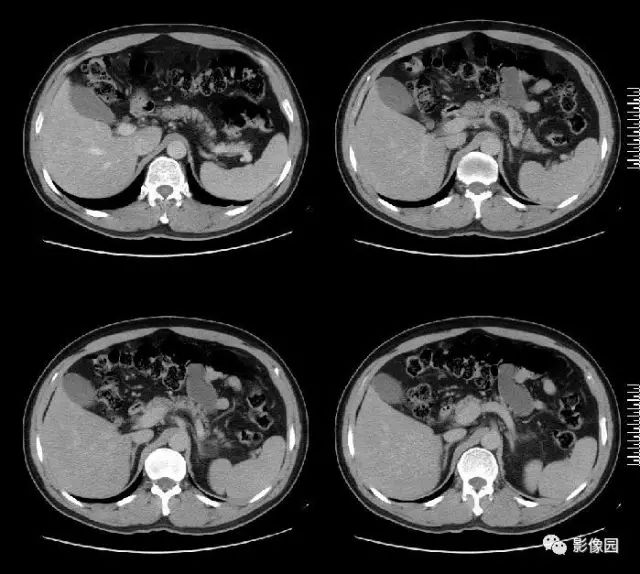

肚肚丫头: 左侧肾上腺见结节状异常密度影,无分叶,边缘光滑,增强扫描呈显著不均匀强化,中心见片状低密度区,考虑:1. 嗜铬细胞瘤;2.腺瘤

【病理结果】左肾上腺嗜铬细胞瘤

影像诊断要点

CT:CT对肿瘤定位可提供较准确信息,诊断准确率高,为常用检查方法。多表现为一侧肾上腺较大圆形或椭圆形肿块,偶为双侧性。直径常为3~5cm,或更大。较小肿瘤密度均一,类似肾脏密度;较大肿瘤常因坏死或陈旧性出血而密度不均,内有单发或多发低密度区,甚至呈囊性表现。少数肿瘤可有高密度钙化灶。增强扫描,肿瘤实体部分明显强化,其内低密度区无强化。